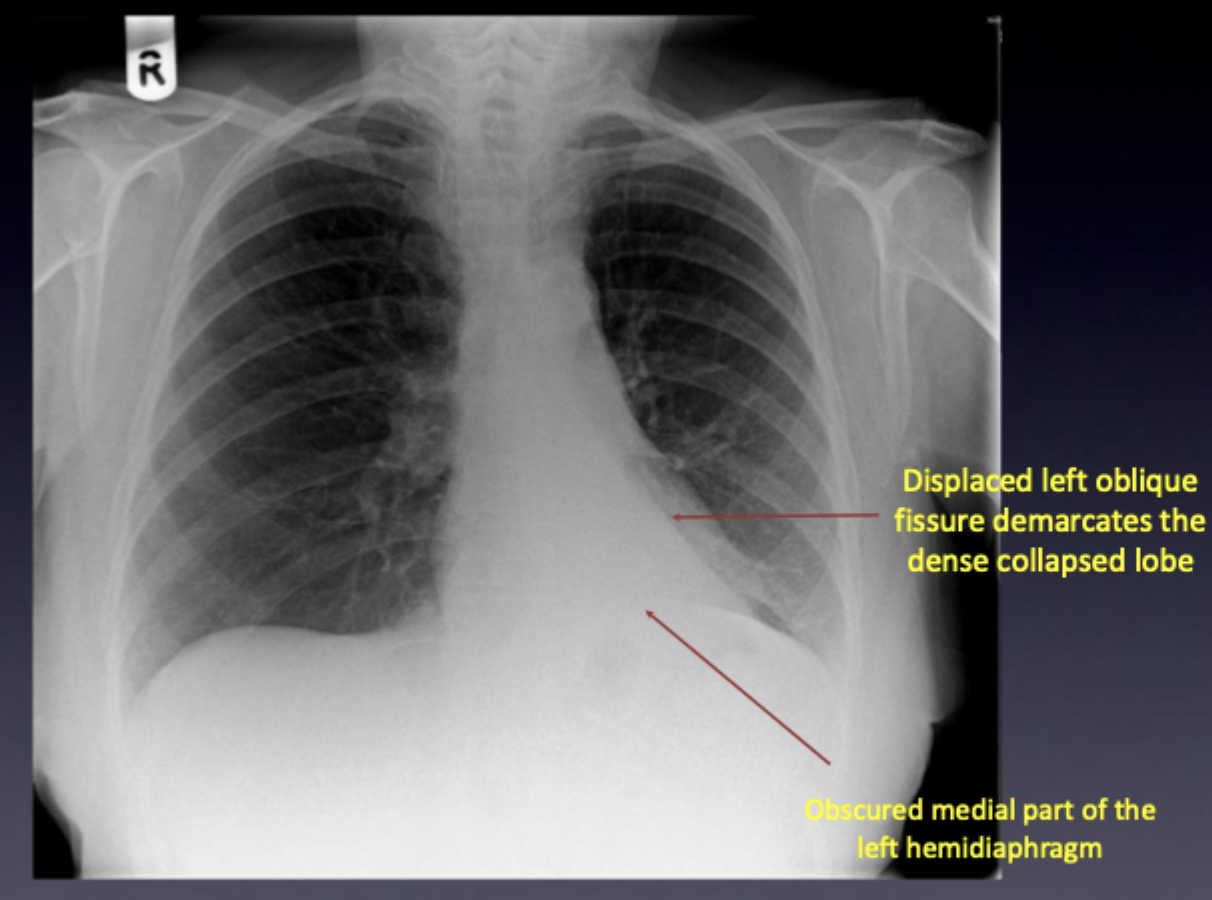

24

Q

What is this ?

A

Left lower lobe collapse

How well did you know this?

What does the Left upper lobe collapse pattern look like ?

Left oblique fissure is pulled anteriorly A well defined lobar edge becomes visible on the lateral view Collapsed lobe abuts the left heart border which becomes obscured on the PA view. Other PA signs include -attenuation of the x-ray beam throughout much of the left hemithorax, seen as a ‘veil like’ opacity -reduced left lung size | Abuts = next to or have a common boundary with.